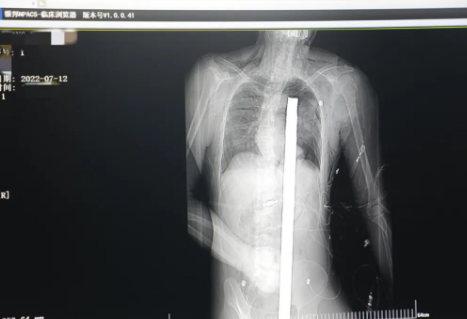

時間就是生命!此時,西安國際醫(yī)學中心醫(yī)院展開了一場與生命賽跑的搶救,第一時間開辟綠色通道,急診X光片及CT顯示:異物經會陰部貫穿盆腔、腹腔到達左側胸腔主動脈弓水平。醫(yī)院創(chuàng)傷中心立即啟動應急預案,劉延彤副院長親臨指揮,下午17點48分,當患者被送達手術室,胸外、心外、肝膽外科、胃腸外科,泌尿外科及麻醉科等多學科專家聯(lián)手對這名工友進行“縱劈胸骨 前外側開胸探查 氣管及主支氣管修補 肺修補 血胸清除 開腹探查止血 腹膜后及盆腔探查......”手術。

情況緊急!術中探查后發(fā)現(xiàn),長120cm直徑3cm的螺紋鋼經患者右側會陰部穿入,傷及直腸,途徑膀胱后方,左側髂總動靜脈之間傷及左腎后,經胰腺后方在肝脾之間穿破膈肌,在下肺靜脈前方穿入左肺穿破氣管及左右主支氣管膜部,止于主動脈弓下水平,穿入體內的部分達到75cm。